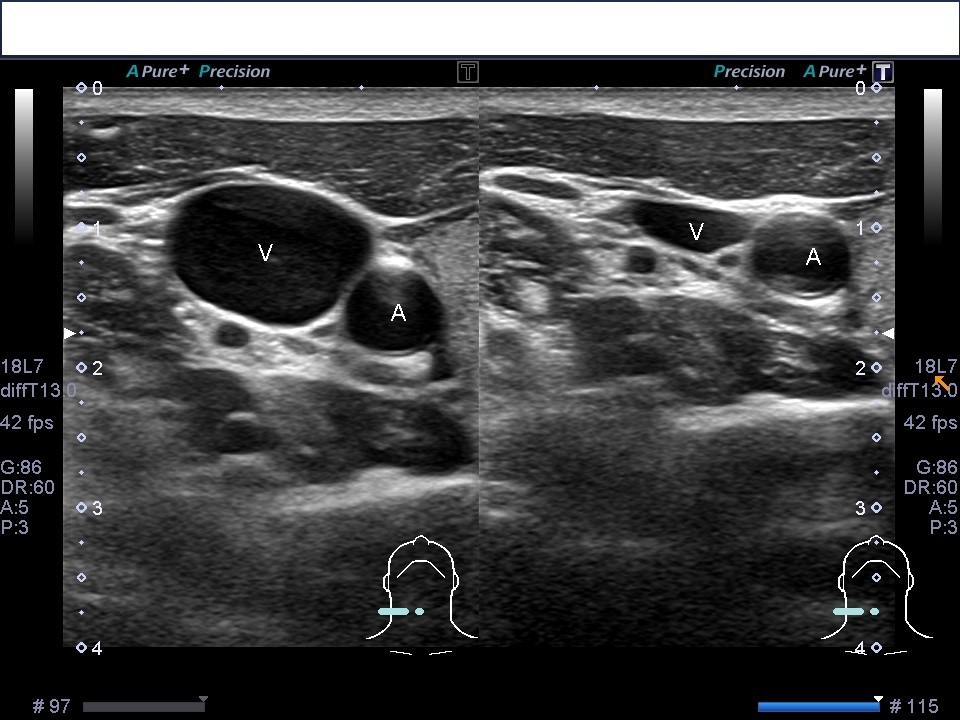

頸部の右内頸静脈と総頚動脈のエコー画像にです。血管はエコーでは黒く映ります。

内側に動脈や甲状腺がみえます。画像を見れば内側に針が向かっていく危険性がわかりますね。

右はプローブを押さえた時の画像です。浅い位置にある静脈は少しの圧排で変形します。ドプラ画像が使えないときは圧排することによって静脈を確認できます。

血管の位置と周りの組織の位置を確認してから、麻酔、穿刺になります。

縦に走査した時の血管の見え方です。静脈の下に動脈が描出されてます。このようなコースでは静脈を貫通した時に動脈の刺さって危険なので、できるだけ動脈が描出されてないコースを探します。なかなか理想的に行かないんですけどね。